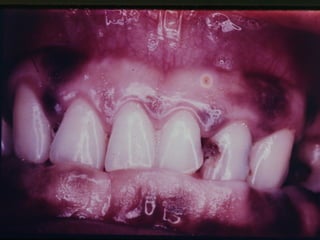

Aspectos ortologicos da mucosa bucal